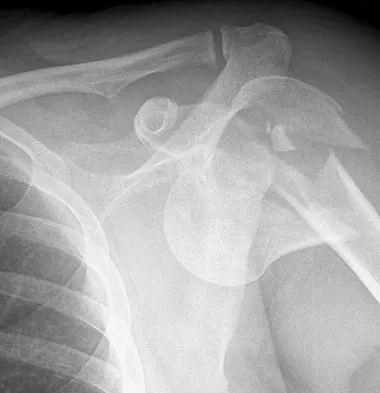

Figure 7 shows the radiograph of an otherwise healthy 65-year-old man who injured his right dominant shoulder while skiing 18 months ago. He did not seek treatment at the time of the injury. He now reports intermittent soreness when playing golf but has no other limitations. Examination reveals full range of motion and no tenderness, but he has slight pain with a crossed arm adduction stress test. He is neurologically intact. Initial management should consist of

The radiograph shows a displaced type II distal clavicle fracture with nonunion. Because the patient's symptoms are minimal, the injury can be treated like a grade III acromioclavicular separation. Present management should consist of ice, anti-inflammatory drugs, activity modification, and perhaps physical therapy. If nonsurgical management fails to provide relief, the surgical options are varied with no uniformity in the literature regarding surgical treatment of this injury. Beaty JH (ed): Orthopaedic Knowledge Update 6. Rosemont, IL, American Academy of Orthopaedic Surgeons, 1999, pp 271-286.